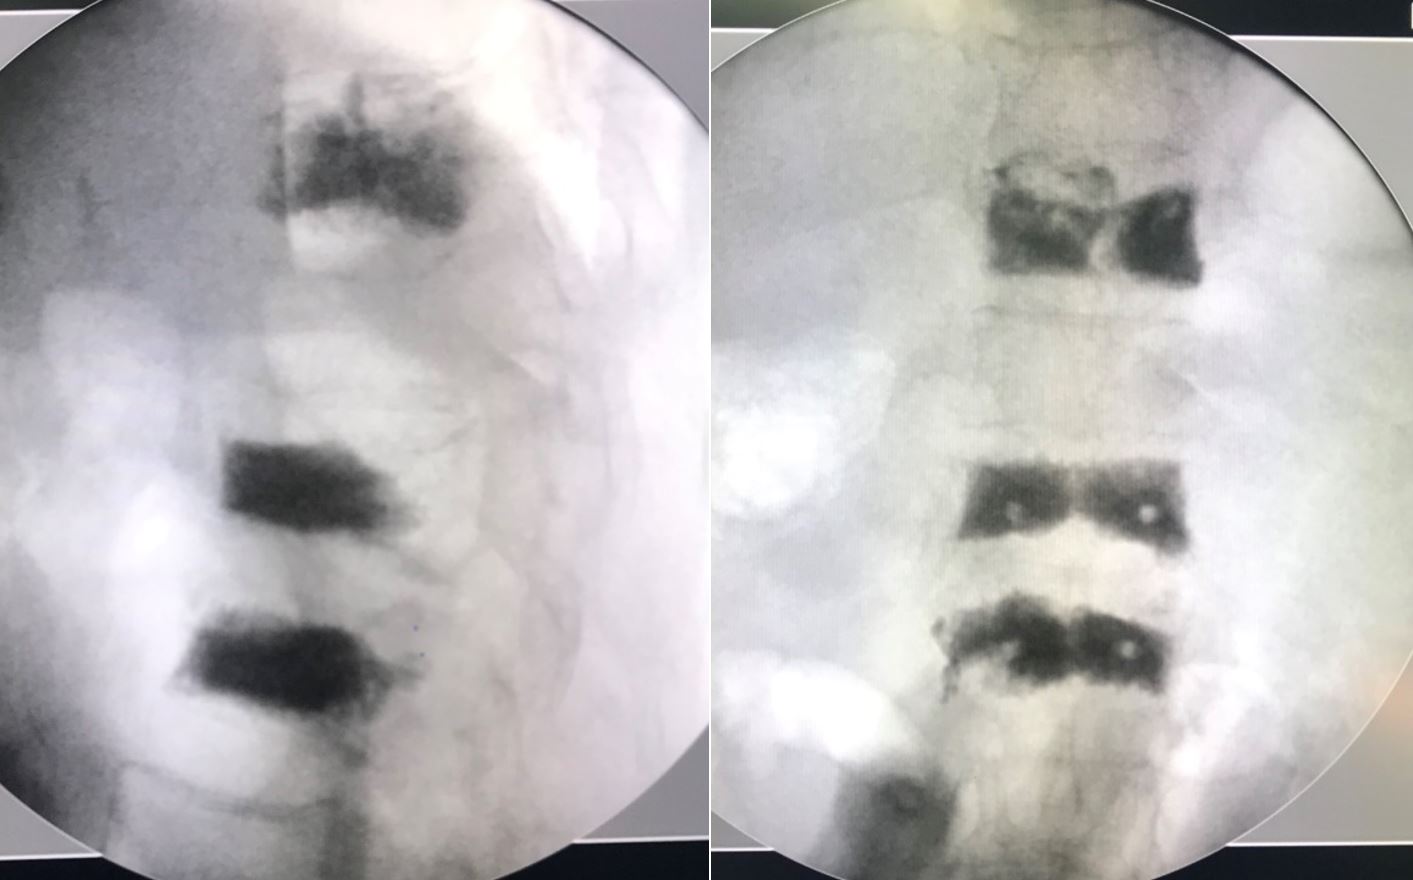

MỘT SỐ HÌNH ẢNH MINH HỌA

Hình 2: Hình ảnh x-quang cột sống sau bơm xi măng